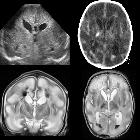

In the immunocompetent adult patient, the pattern is quite typical and manifests as a bilateral asymmetrical involvement of the limbic system, medial temporal lobes, insular cortices and inferolateral frontal lobes. The basal ganglia are typically spared, helping to distinguish it from a middle cerebral artery infarct.

MRI

Affected areas, however, have a similar appearance regarding signal characteristics:

- T1

- may show general edema in the affected region

- T2

- hyperintensity of affected white matter and cortex

- DWI/ADC

- more sensitive than T2 weighted images

- restricted diffusion is common due to cytotoxic edema